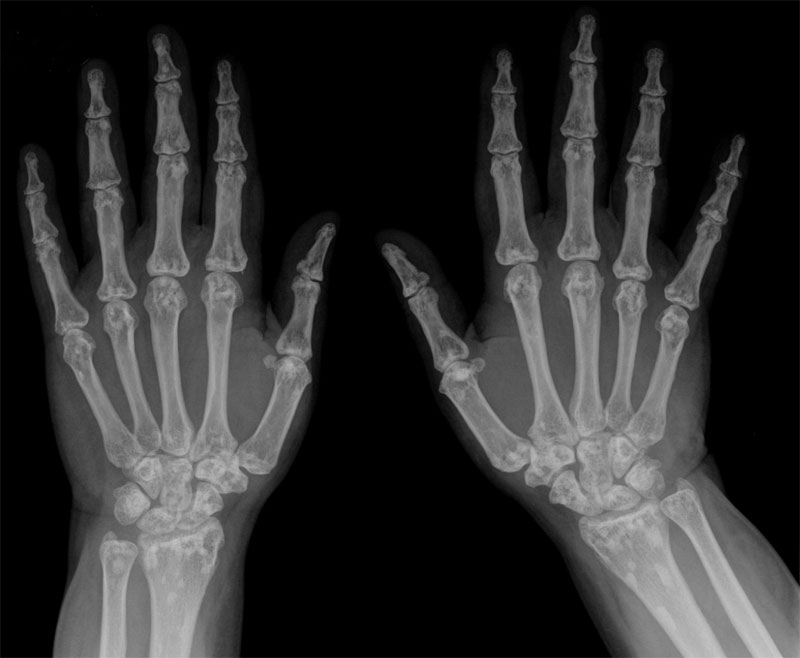

Denotes a concentration of mature compact (cortical) bone within the cancellous bone (spongiosa) and can be referred to as condensing osteitis. This benign lesion may be located anywhere in the skeleton but has a predilection for the long bones and pelvis. It is probably congenital in nature and suggests failure of resorption during endochondral ossification.

A harmless growth inside a bone, usually in the skull or in a long bone.